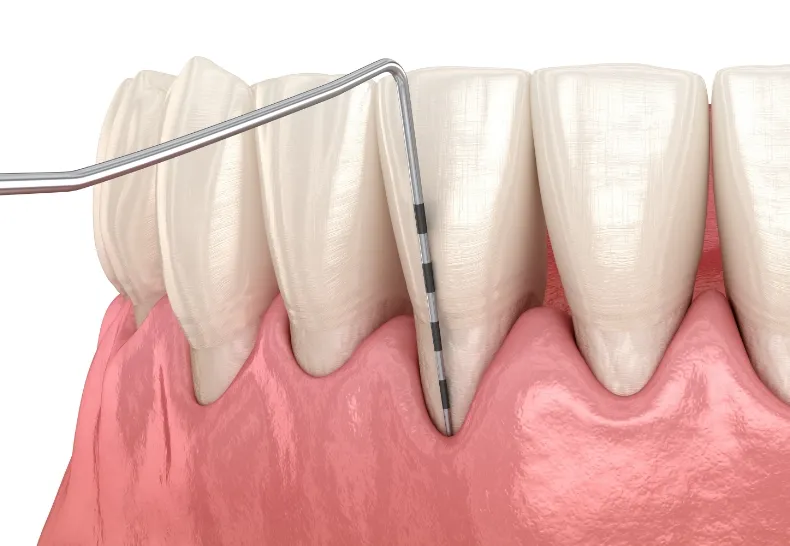

プロービング検査

歯と歯肉の間にできる歯周ポケットの深さを測り、歯周病の進行度を調べる検査です。プローブという針状の器具を溝に差し込んで検査します。また、このときに出血の有無や歯肉の弾力などを合わせて確認します。